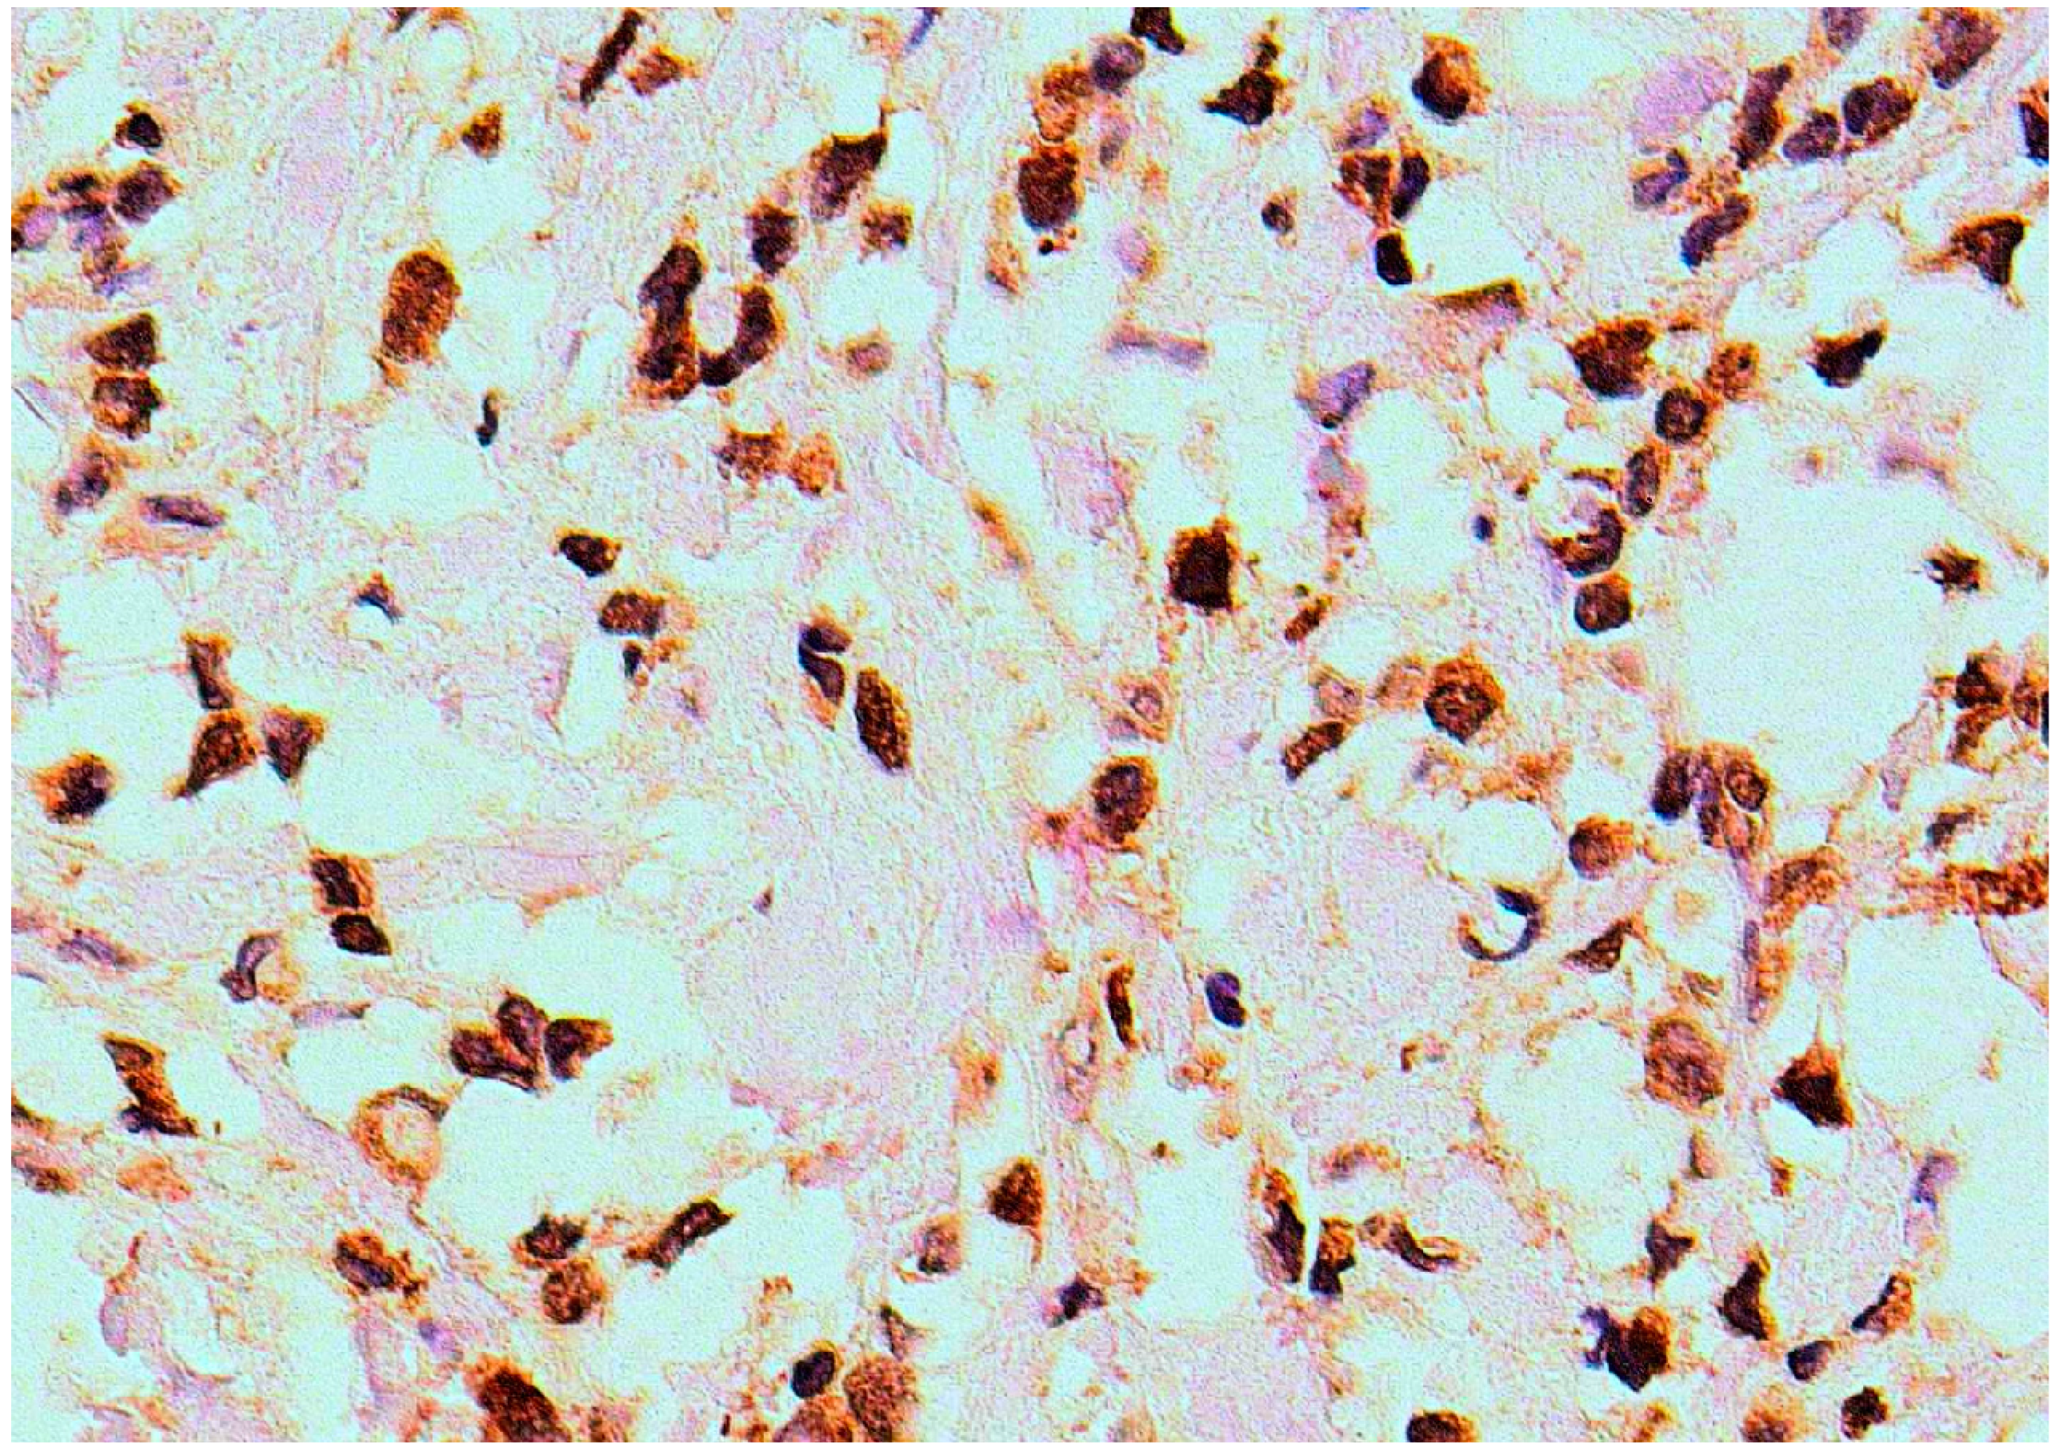

Increased HDAC-2 expression was observed in 11 (27.5%) of the 40 cases of triple negative breast cancer that showed positive HDAC-2 staining (Figure 2 and Table 3). Tumor-free tissue sections were negative for HDAC-2 expression.

Figure 2.

HDAC-2 immunohistochemical expression in triple negative breast cancer tissue (×200).